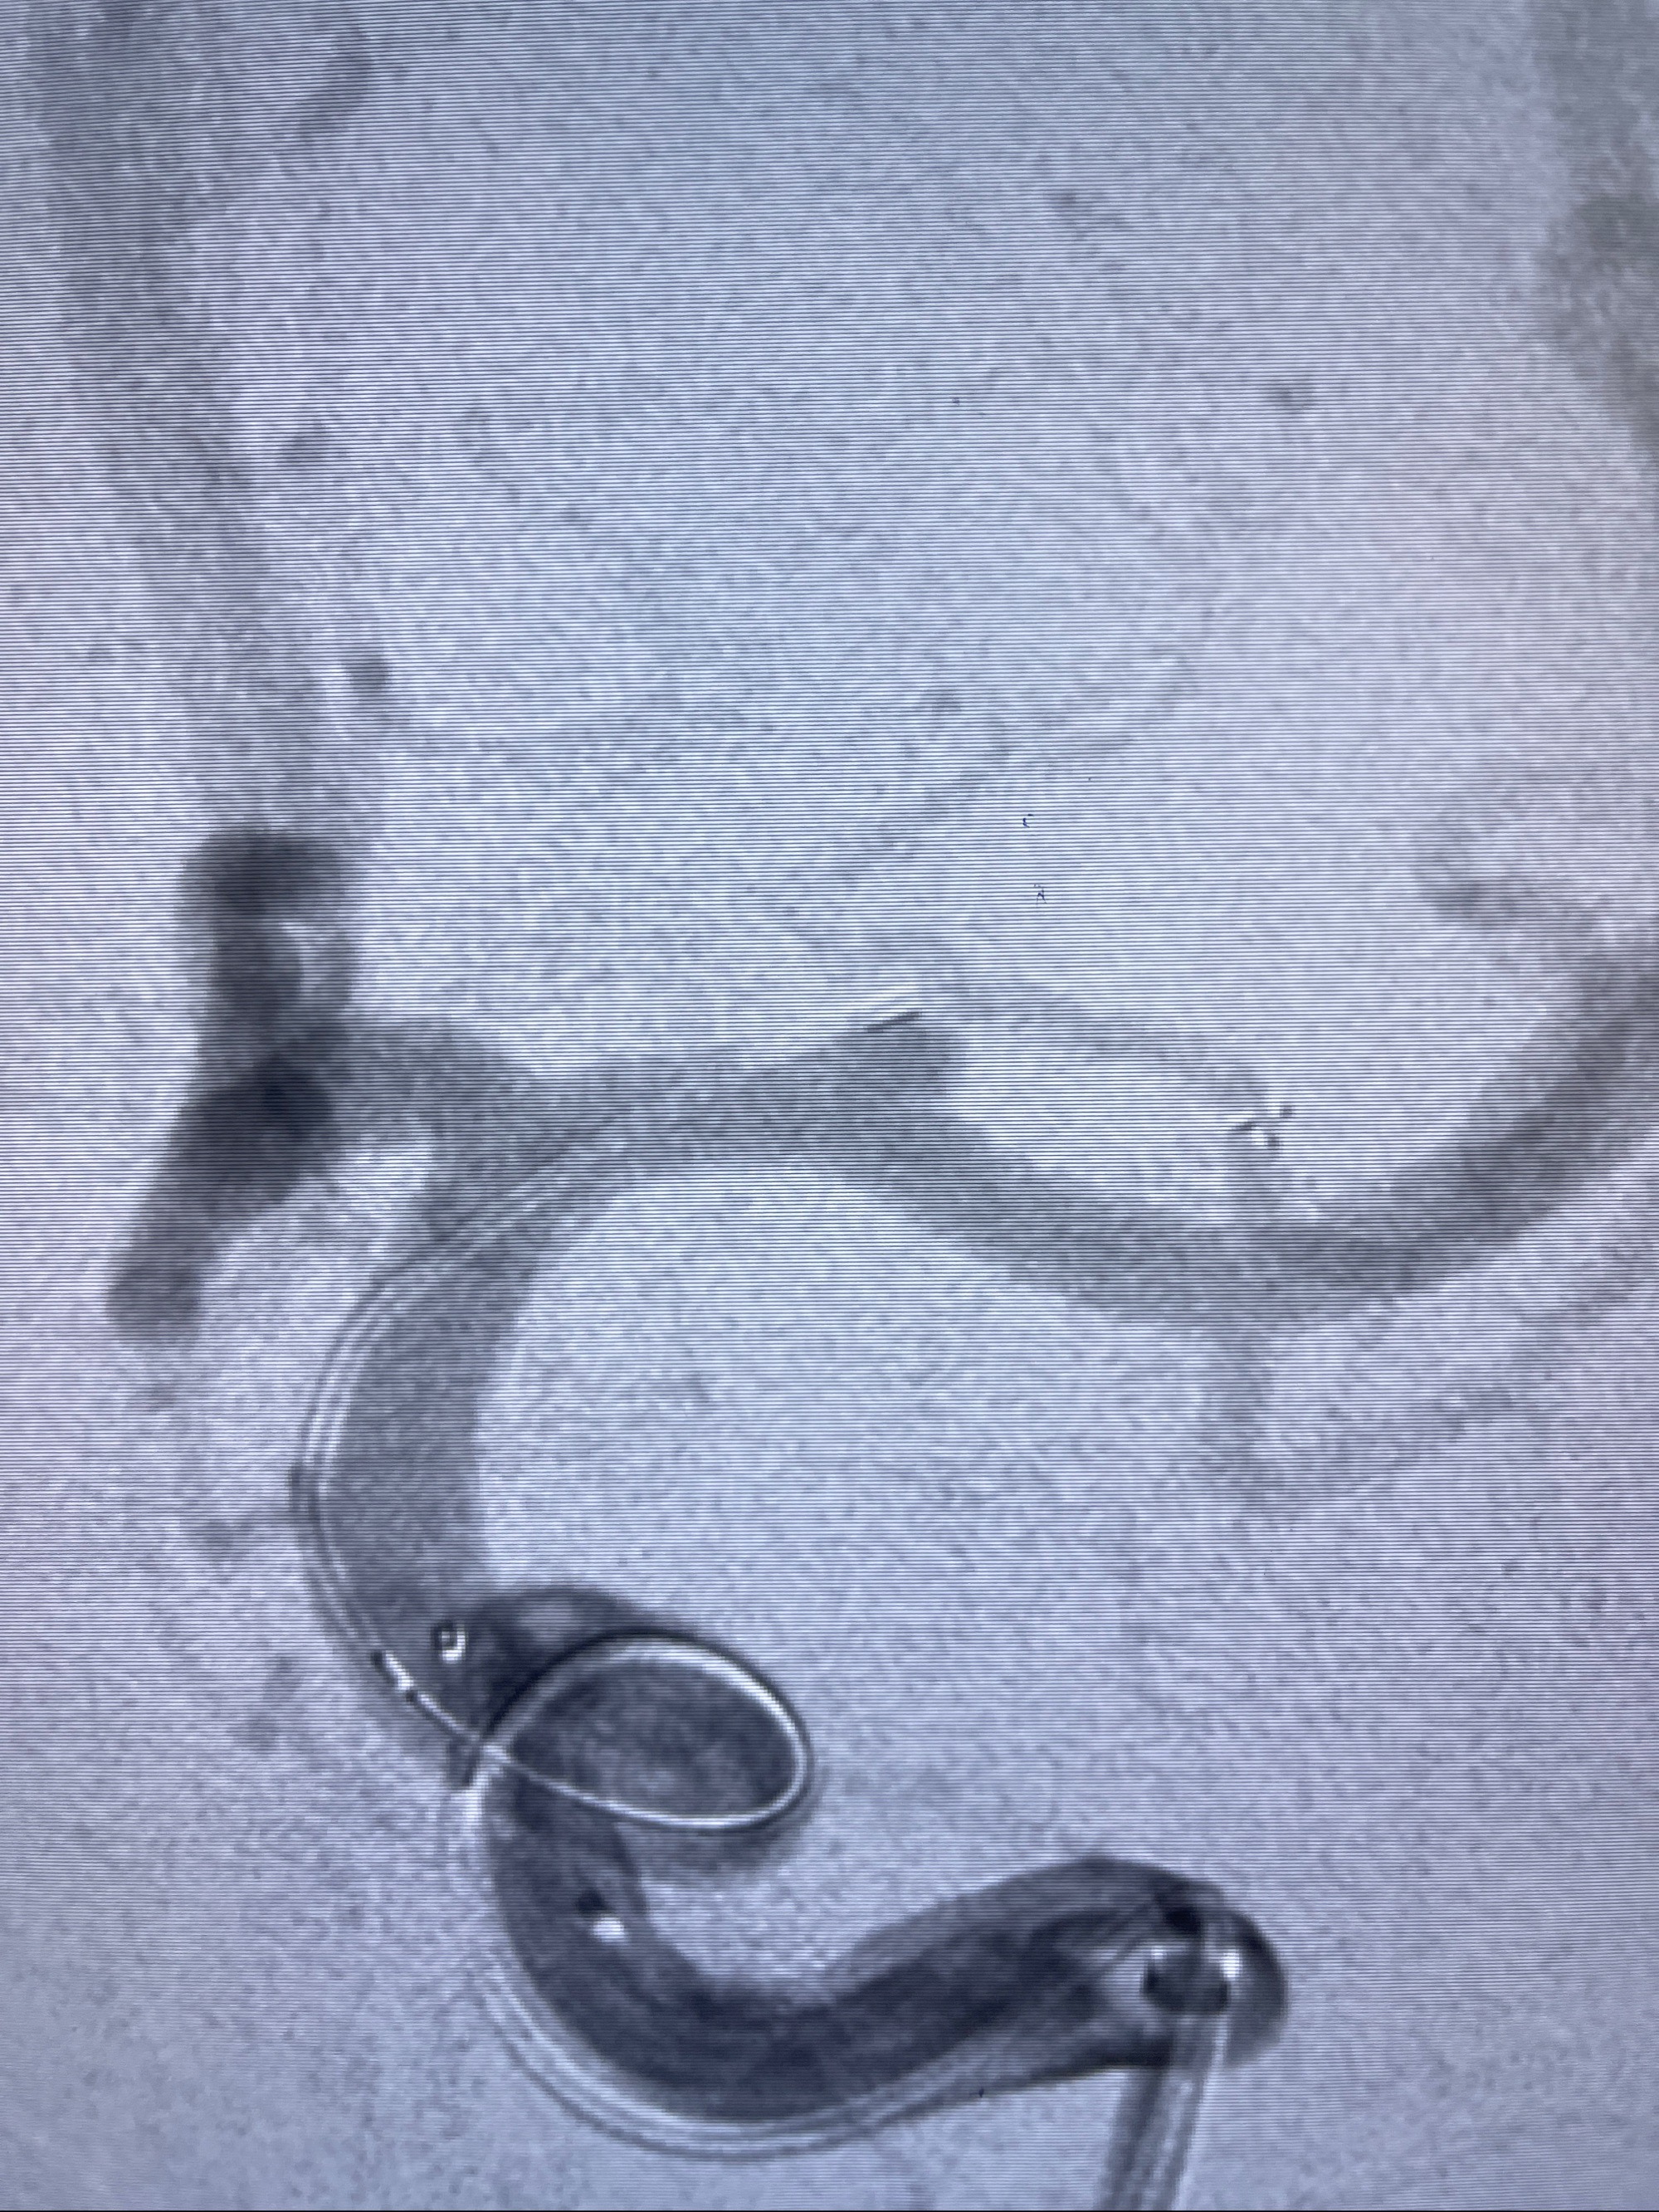

2023-08-14DSA:

左侧大脑中动脉动脉瘤,约2.6-2.8-3.4-2mm大小(瘤颈部、瘤体部、瘤高)

1.左侧大脑中动脉动脉瘤,约2.6-2.8-3.4-2mm大小(瘤颈部、瘤体部、瘤高)

2.外科手术夹闭or介入支架辅助栓塞